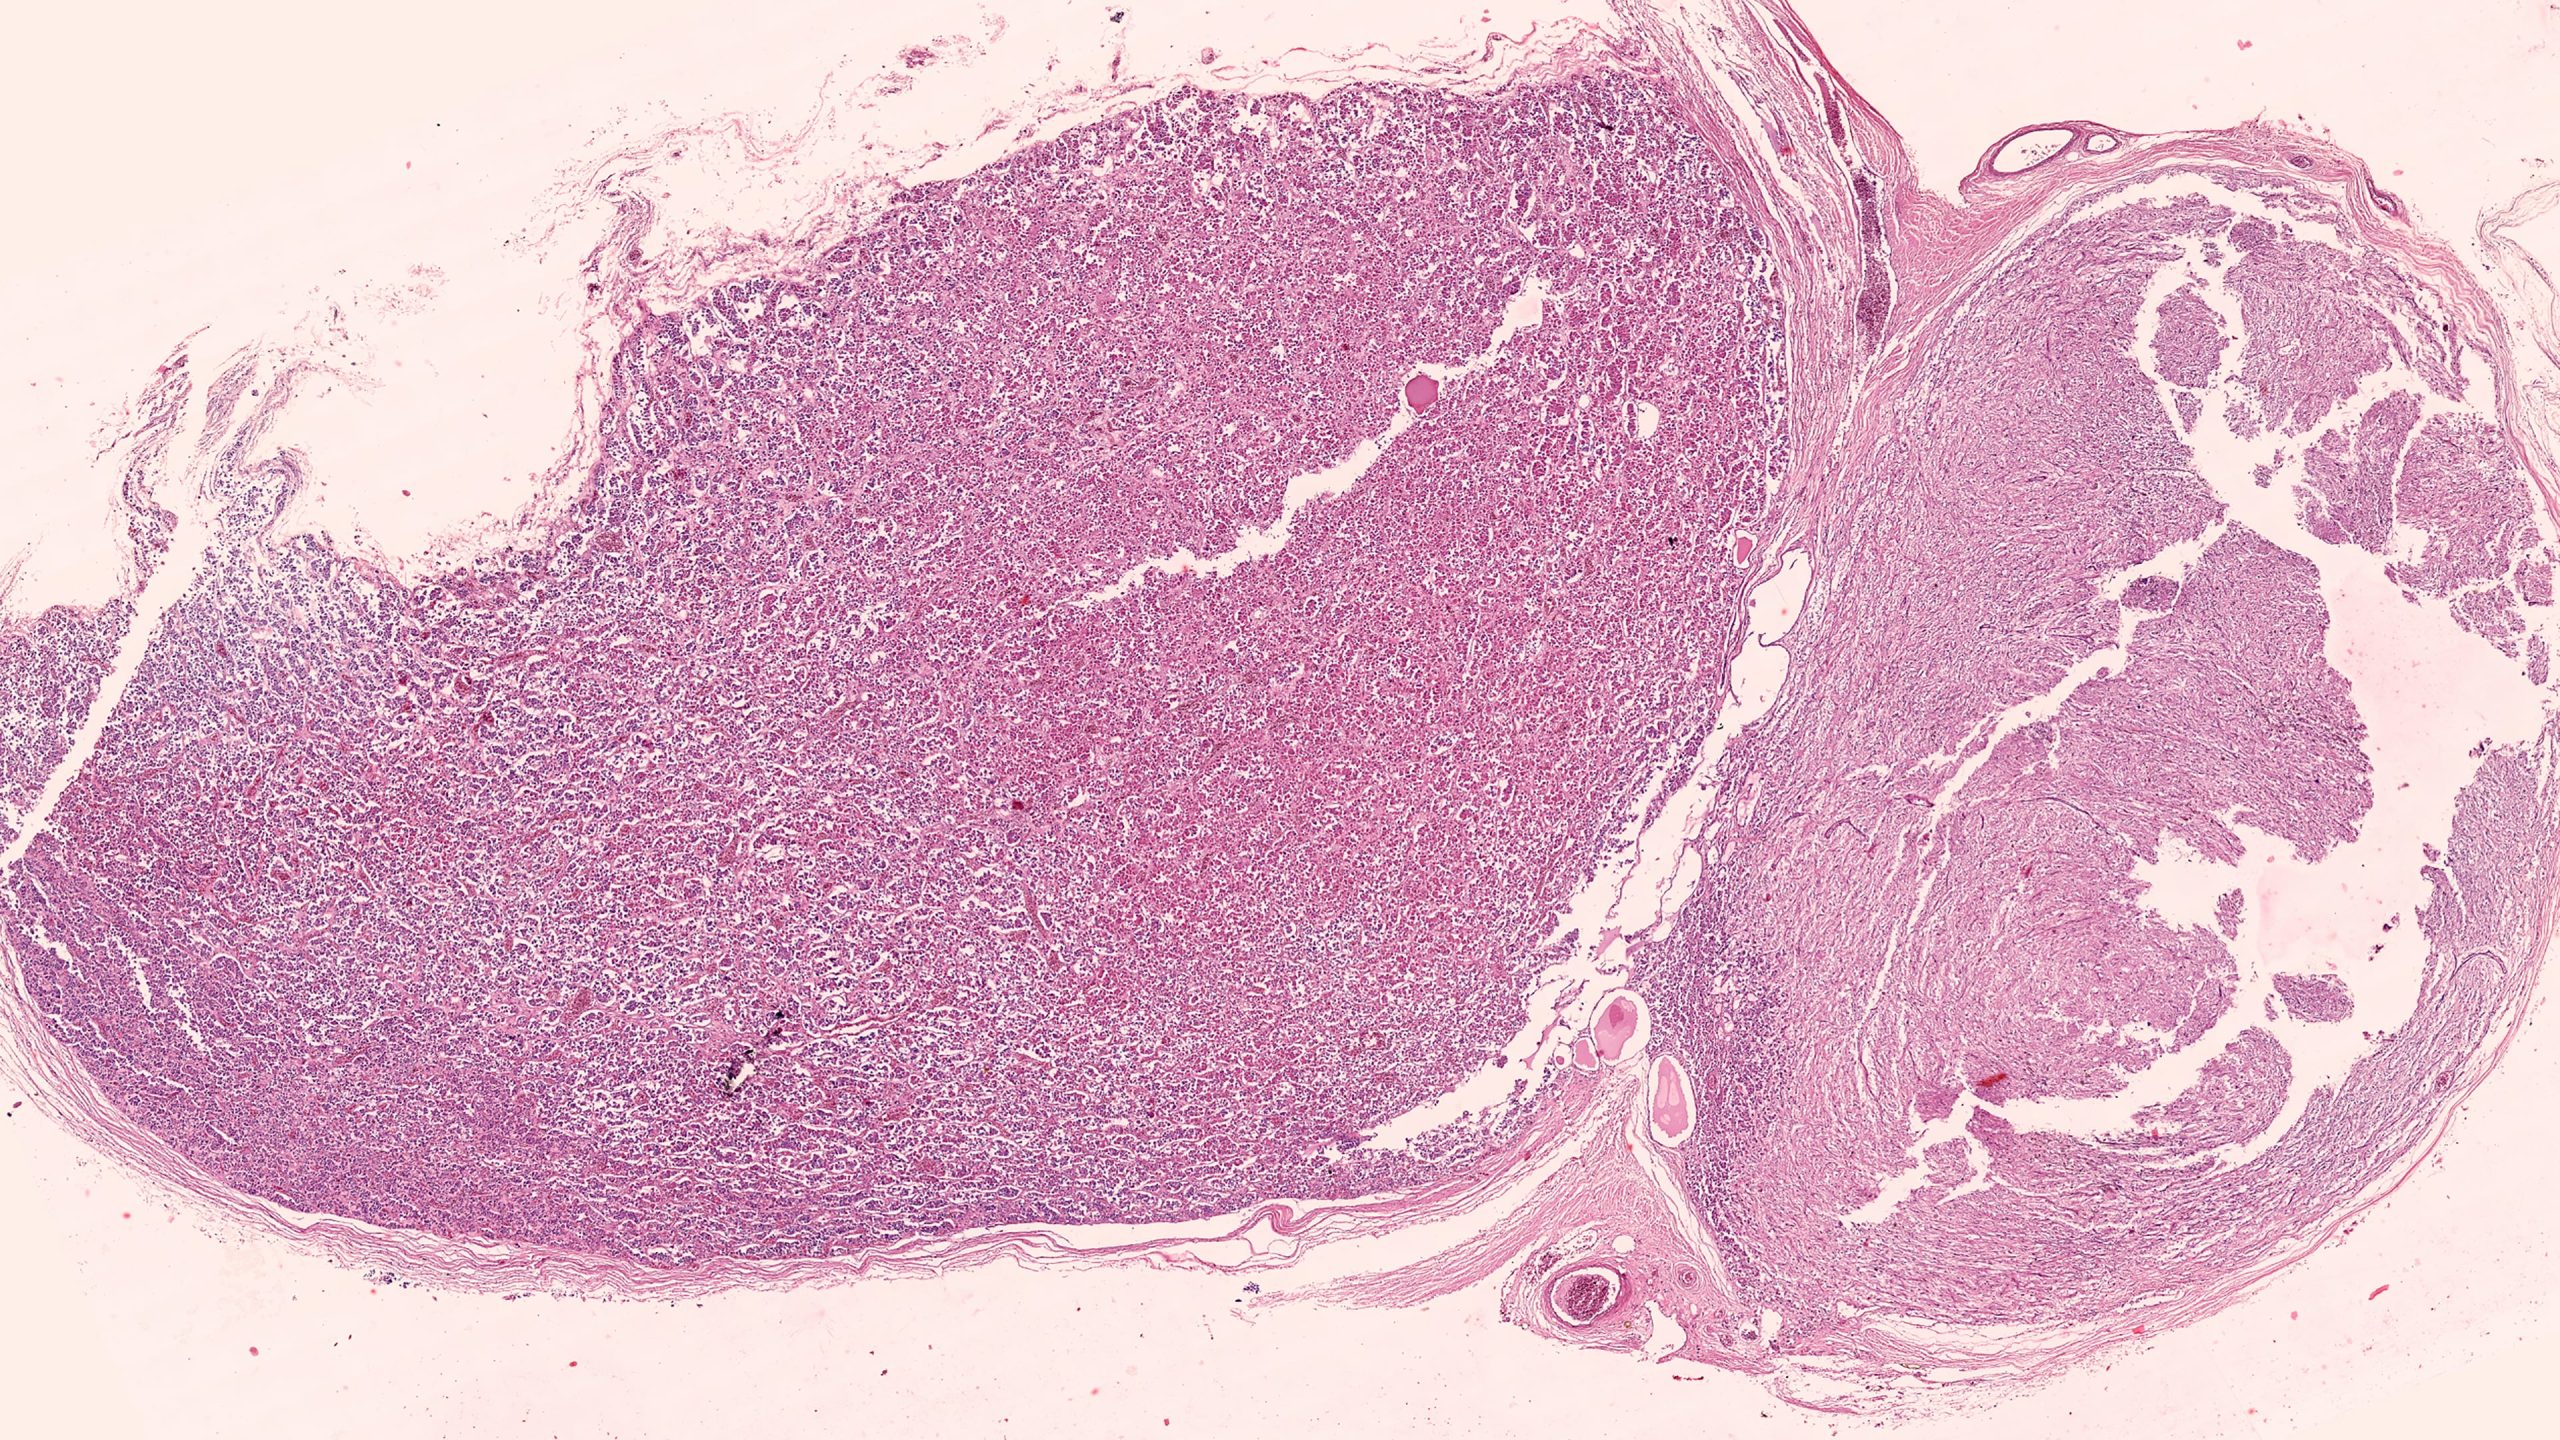

Pituitary 4X